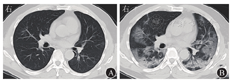

病变发生于两肺各部位,28例患者胸部CT检查主要表现为磨玻璃影21例(75.0%),边缘模糊18例(64.3%),斑点、斑片影17例(60.7%),部分肺纹理增粗、紊乱7例(25.0%),可见条索影7例(25.0%),局部支气管扩张2例(7.1%),淋巴结增多、增粗、血管影、结节影与无壁透亮区各1例(3.6%)。见图1。1例重型肺炎患者入院时两肺纹理增多,两肺内见多发斑片状磨玻璃影,边缘模糊,6 d后肺部病变短期内进展迅速,表现为两肺弥散病灶,磨玻璃影范围增大,双侧胸膜增厚,见图2。